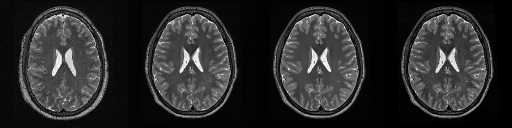

HCP T2w dataset

We utilize images from the publicly available Human Connectome Project (HCP) [51] T2-weighted (T2w) images dataset for the task of compressed sensing, which contains brain images from 47 patients. The HCP dataset includes cross-sectional images of the brain taken at different levels and angles.

Compressed sensing

We train a flow-based model from scratch on 10,000 randomly sampled images, utilizing the ncsnpp architecture [9] with minor adaptations for grayscale images. We employ compression rates , meaning . The measurement operator is given by a subsampled Fourier matrix, whose sign patterns are randomly selected. We evaluate our reconstruction algorithm’s performance on 200 randomly sampled test images.

We present the quantitative and qualitative results of compressed sensing in Tab. 1 and Fig. 4, respectively. As shown in Tab. 1, our method consistently achieves the best performance across varying compression rates . In Fig. 4, our method produces reconstructions that are more faithful to the original images, with fewer artifacts, leading to higher accuracy and clearer details.